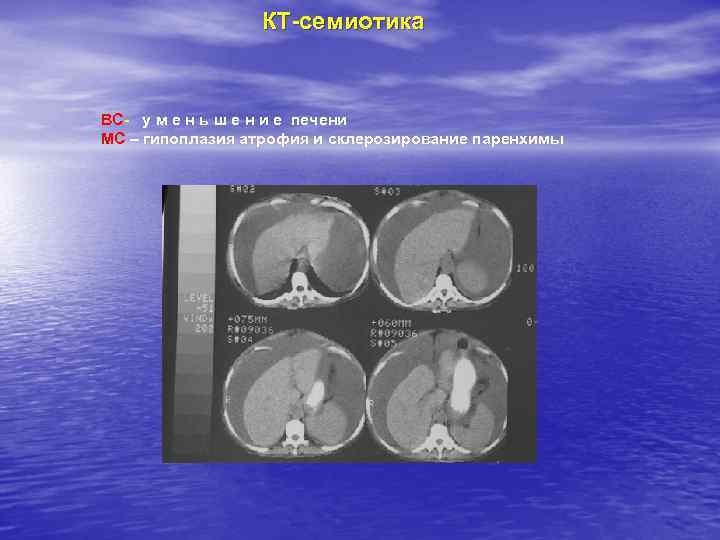

КТ-семиотика ВС- у м е н ь ш е н и е печени МС – гипоплазия атрофия и склерозирование паренхимы